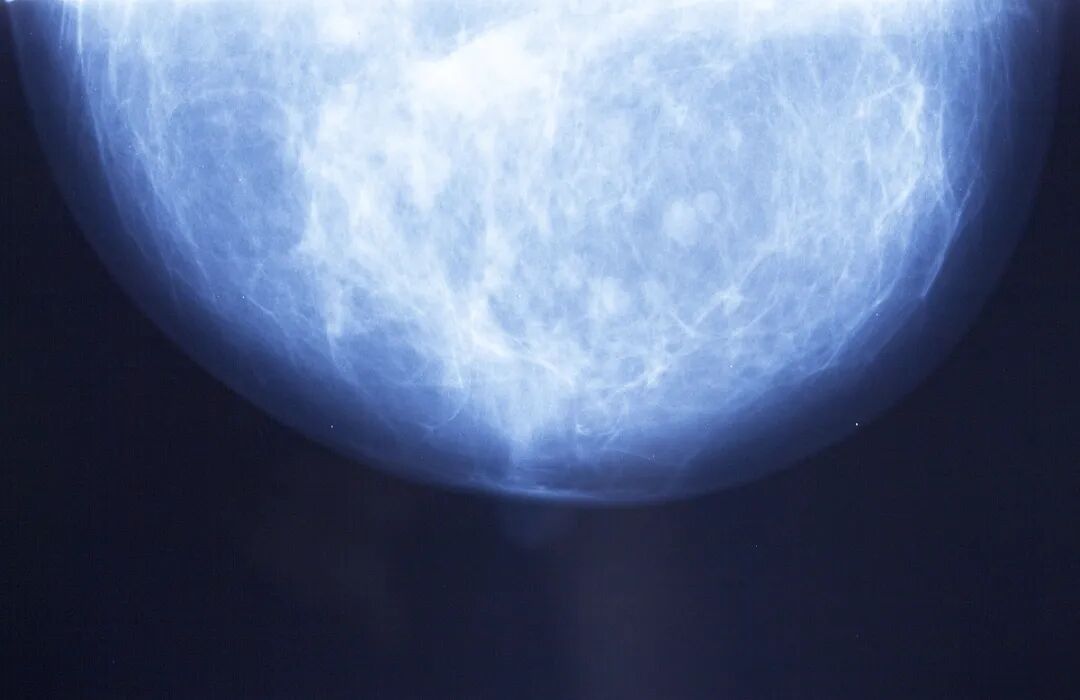

《细胞》:乳腺癌的转移灶,我们看错了!科学家发现,乳腺癌转移灶不是无序的肿块,而是有独特的空间结构丨科学大发现

这项研究借助于多种分子生物学和成像技术手段,发现在不同部位的转移灶中,乳腺癌的组织和扩张,不是混乱无序的自由生长,而是激活了一套名为“转移性小梁形态发生”(MTM)的基因程序;这套程序会启用胚胎发育时期的分支形态发生机制,使癌细胞在转移灶中构建出复杂的3D小梁状结构,而非原发灶常见的紧凑肿块。

既然不同亚型乳腺癌转移灶中的癌细胞都启动了FMM程序,那转移灶的三维结构肯定也是有特定组织的。借助于AI驱动的3D成像技术,研究人员重建了转移灶的三维形状和微观结构。果不其然,在不同组织器官的转移灶中,转移性乳腺癌细胞形成了一个三维晶格状结构。重要的是,这种结构并非由组织器官微环境所致,而是转移性乳腺癌的内在能力。

既然如此,那转移风险高的原发灶应该也存在小梁状结构。研究结果显示,所有预期会发生转移的原发肿瘤均呈现出与远处转移灶相似的小梁状结构,而非转移性原发肿瘤则保持着致密、实性的结构。